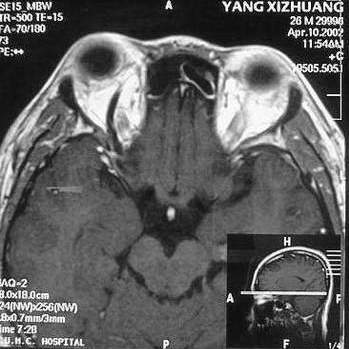

MRI及增强结果如下:

患者压颈及其它Valsava试验结果阴性。从MRI分析,在T1、T2、T+C检查该支血管均为明显流空现象,说明该血管血流速度很快,而从走行和分布看,眼上静脉可能性很大。也许也不能除外异常的眼动脉或异常血管。眶内主要可能的血管病变包括颈内动脉海绵窦瘘(高流窦)、AVM、眼眶静脉曲张、海绵状血管瘤、静脉性血管瘤、毛细血管瘤和眶内动脉瘤。。 1、颈内动脉海绵窦瘘:该患者临床有一部分支持该诊断。但从影像分析,海绵窦未见明显扩张;眼外肌未见明显充血扩张的长T1、长T2信号;颈内动脉海绵窦瘘常可见继发到血栓,可见到短T1、长T2的血栓信号。 2、眼眶静脉曲张:该疾患一般常见于小儿。该患大多数会出现Valsava试验阳性,间歇性突眼。不符合该患。影像学检查,于曲张静脉内常可见血栓和静脉石。所以不符合该患。 3、AVM:患者目前的影像学资料尚不全面,但可符合该诊断。临床上改病常见于30岁左右年轻人,单侧发病,于本患较符合。问题在于临床没有明确的血管杂音,似乎难以解释。 4、该患影像学与海绵状血管瘤差别很大,所以可基本排除此诊断。 5、静脉性血管瘤和毛细血管瘤:MRI中等T1、长T2信号,较易与本病鉴别。 6、眶内动脉瘤:我觉得患者并不能排除本病,但同样,由于波动性阴性,似乎也难以解释。 纵上所述:本人觉得,患者AVM可能性较大,同时不能除外眶内动脉瘤。 关于进一步检查,我觉得DSA价格过于昂贵。是否可先进行彩色多普勒检查,首先可以明确是静脉系统还是动静脉瘘抑或是动脉瘤。第二步,可进行MRA检查,可以清楚地显示海绵窦地相关关系,并可借此诊断或排除颈内动脉海绵窦瘘。如还需第三部检查,可进行MRV检查,对静脉系统进一步评价。三种检查总共的费用2000多圆,但给予我们的信息量已经很丰富了。 敬请各位医师提出自己的见解。 谢谢!